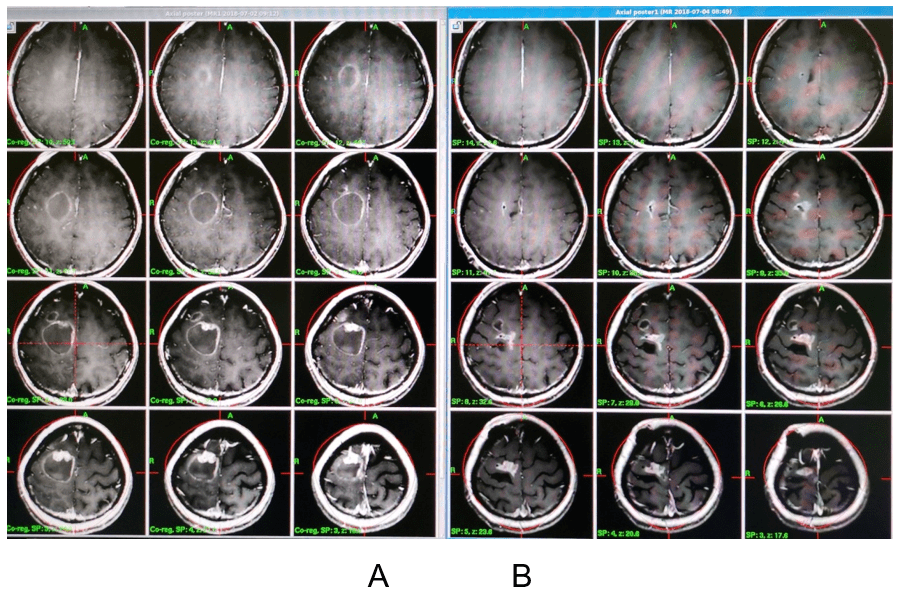

研究孙君昭张剑宁立体定向ommaya囊植入联合伽玛刀治疗颅内大型囊性

图片尺寸901x601

图片尺寸799x518